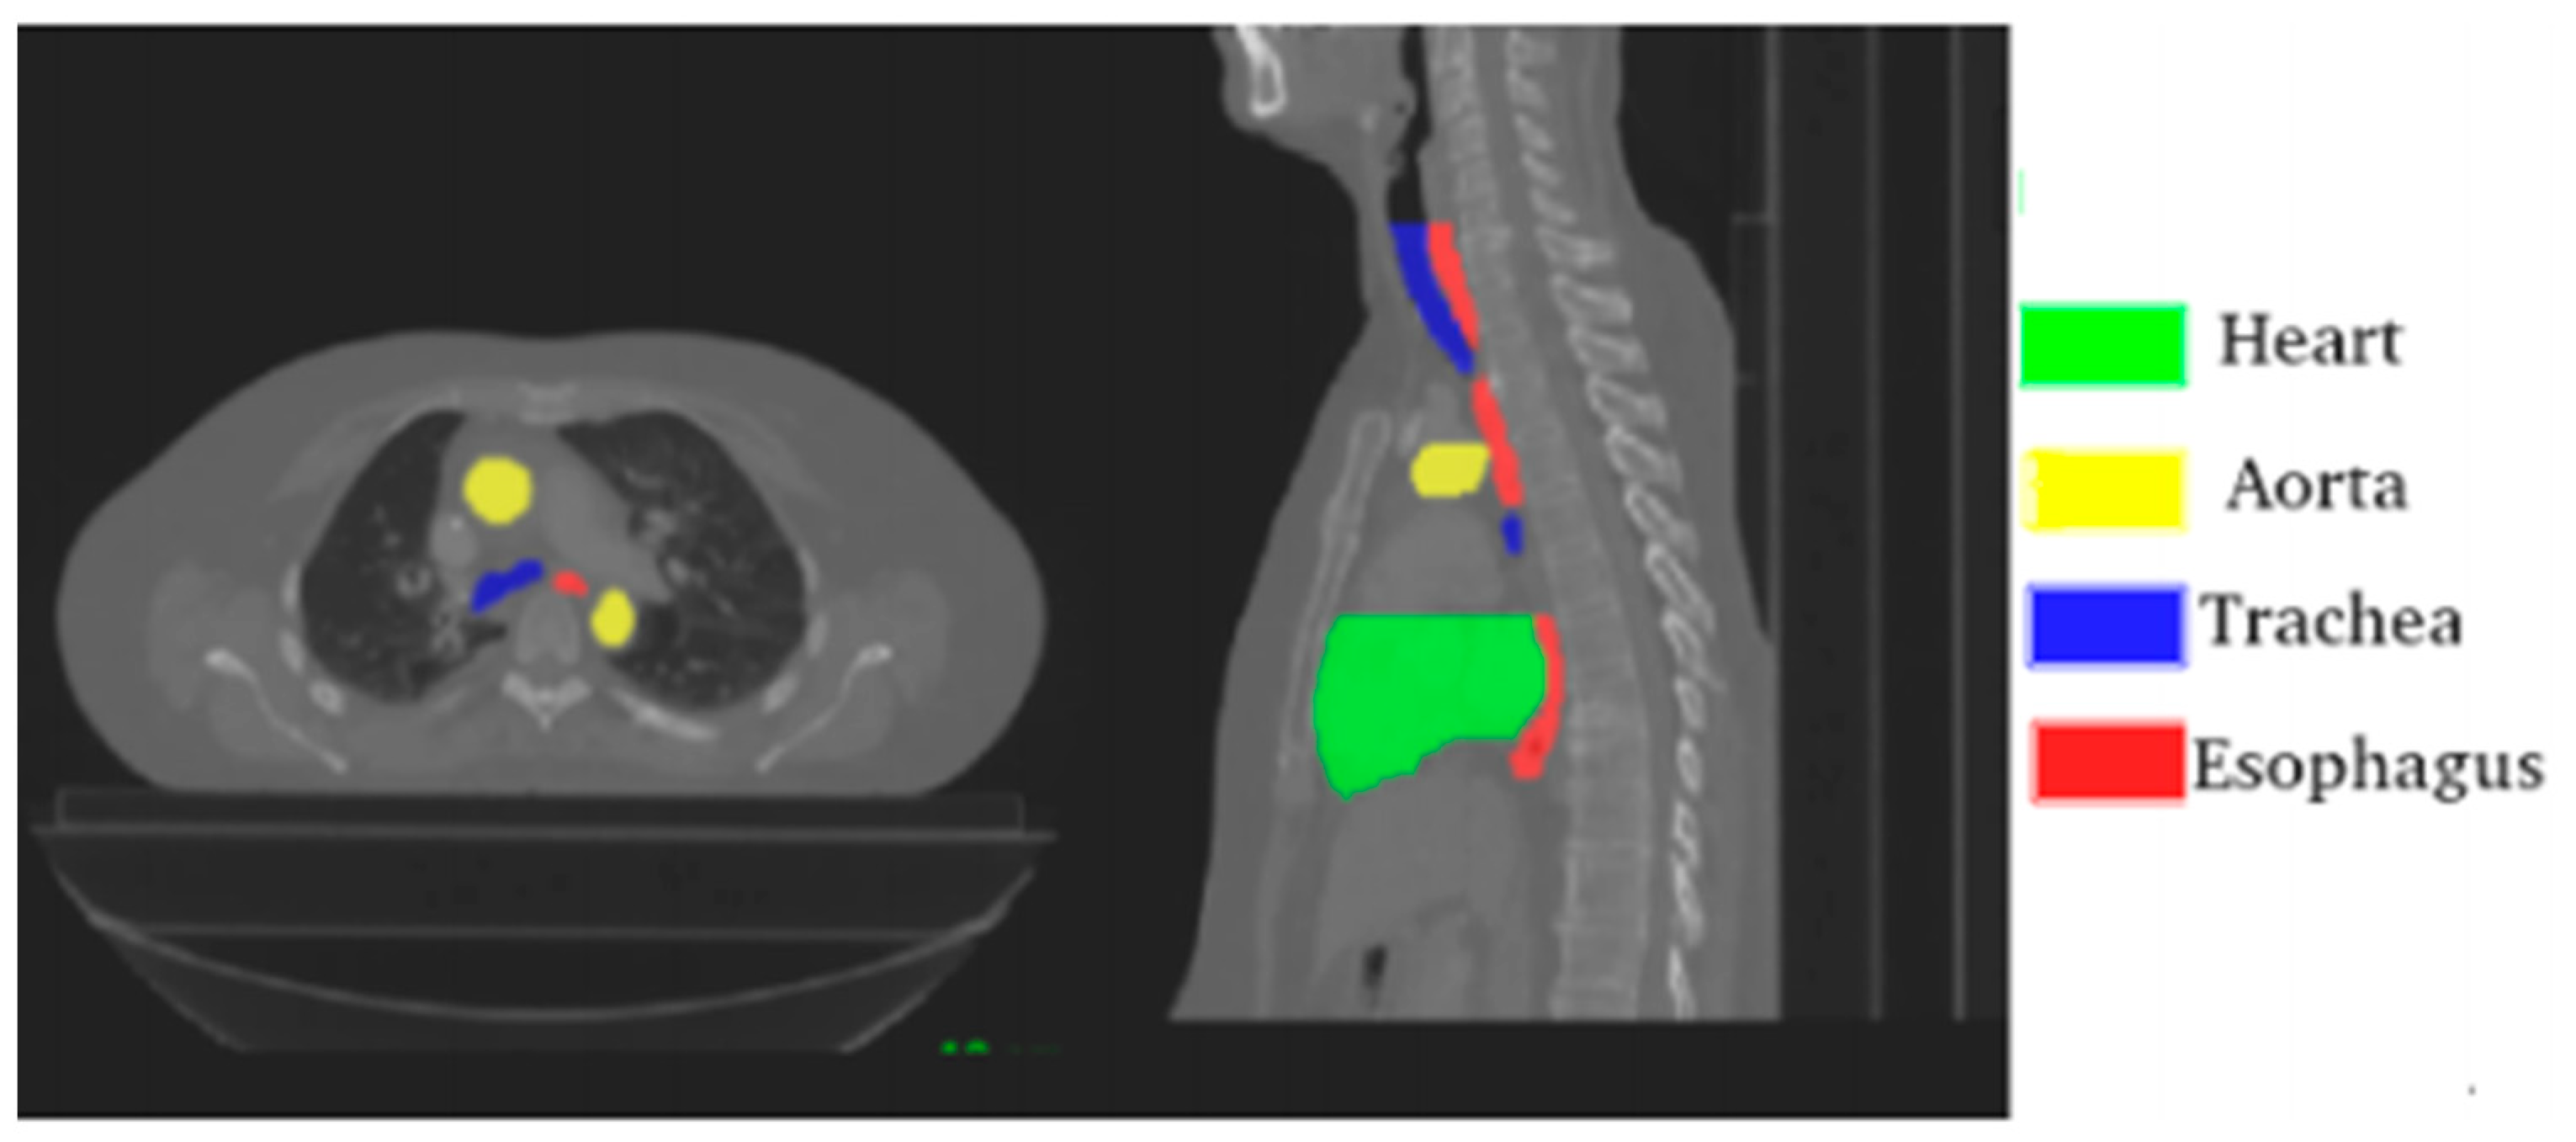

The challenge provides 40 CTs “with manual segmentation while the test set contains 20 CTs. The CT scans have 512 × 512 pixels size with in-plane resolution varying between 0.90 mm and 1.37 mm per pixel, depending on the patient. The number of slices varies from 150 to 284 with a z-resolution between 2 mm and 3.7 mm. The most frequent resolution is 0.98 × 0.98 × 2.5 mm3” [39]. Figure 1. is a visual representation of one of the CTs provided by the challenge.

Figure 1.

Axial and sagittal planes with annotated organs; source Lambert et al. [39].